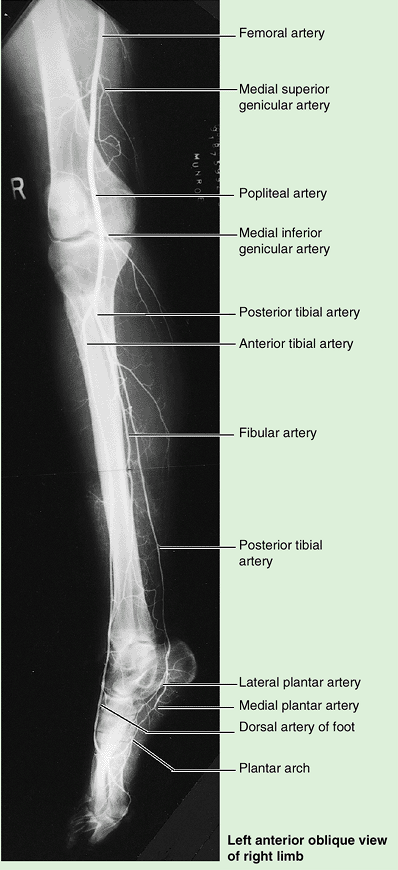

articulates with the condyles of the femur superiorly and the talus

inferiorly and in so doing transmits the body’s weight. The fibula

mainly functions as an attachment for muscles, but it is also important

for the stability of the ankle joint. The shafts (bodies) of the tibia

and fibula are connected by a dense interosseous membrane composed of

strong oblique fibers.